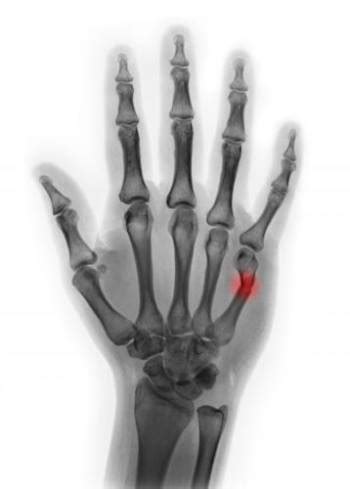

Frattura scomposta alla base e composta al 5 metacarpo mano destra. Per fratture scomposte che non si riescono a ridurre correttamente (cioè se i frammenti non rimangono allineati) può essere necessaria un'operazione. Mi hanno messo il gesso che devo togliere a distanza di un mese, ovvero il 7 febbraio.

Salve ho subito una frattura composta al 5 metacarpo,mi hanno messo il gesso per 25 giorni e me l hanno tolto senza farmi i raggi ,dopo 2 settimane ho ancora dolore forte proprio nel punto dove c era la frattura ma nn è gonfio,e normale? Rivalba, nel frontale con il tir vettura distrutta: Alla rimozione dopo 40 giorni,il paziente presenta rigidità a tutta la mano, in particolare al 4° e 5° dito. Secondo voi facendo un po' di fisioterapia, quei 10 giorni che. Operato dopo una settimana, la frattura viene sintetizzata con 2 fili di k. Riapre dopo due mesi, scivola sull'igienizzante e si frattura il polso: Quesito posto 12 agosto 2016 in ossa del metacarpo da sibi. Da 8 ossa brevi divise in due file metacarpo : Se la frattura è scomposta, significa che l'osso non solo si è rotto, ma si pure spostato dalla sua sede naturale. La rivista nasce nel dicembre del 2004 con l'intento di portare alla luce artisti emergenti considerati di qualità, attraverso una selezione che viene attuata dal comitato redazionale. Nel fatto che una settimana fa mi sono rotta la testa del 5 metacarpo della mano. Mi hanno ingessato le ultime 2 dita. In conseguenza di un impatto ,a pugno chiuso,le ossa metacarpali possono fratturarsi e in particolare il 4° ed il 5°. Hai fratturato il v metacarpo? L'autista se la cava con la frattura di una gamba. Quello che vorrei gentilmente chiedere, riuscirò a recuperare la funzionalità della mano entro il 28 agosto 2010? Come si può sviluppare una frattura al metacarpo?